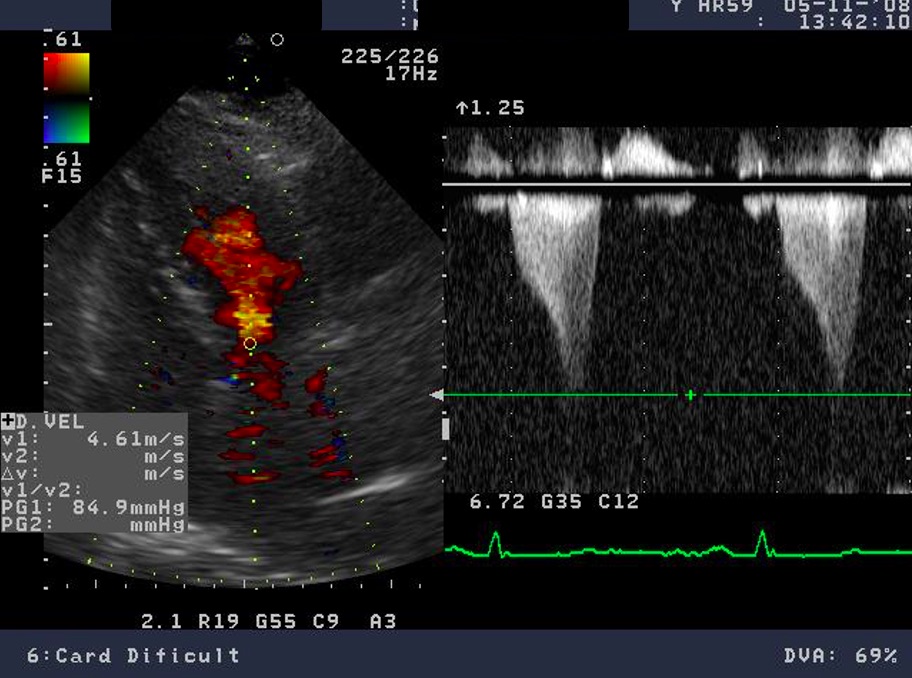

Doppler echocardiography allows assessment of the intraventricular gradient and associated mitral regurgitation. One specific feature is the variability of the LV outflow gradient according to the hydration status, heart rate, the Valsalva maneuver (preload), and blood pressure (afterload). Conditions or pharmacologic interventions that increase preload and increase LV end-diastolic volume may reduce LVOT obstruction. Reduced preload and tachycardia responsible for a reduction in LV end-diastolic volume are associated with an increase in intraventricular gradient. Stress echocardiography is a method that employs different agents (exercise, dobutamine, isoproterenol, amyl nitrite) which alter LV diastolic volume, to highlight the dynamic intraventricular gradient [5, 27, 33]. The degree of mitral regurgitation severity in HCM can vary from mild to severe. The mechanism of mitral regurgitation is related to the geometry change of the valve due to the malposition of the anterolateral papillary muscle, the abnormal attachment of primary chordae tendineae and SAM. The latter is favored by the elongated leaflets of the mitral valve which are a usual feature of the mitral valve in HCM. Moreover, some studies establish a direct linear relationship between the left ventricular outflow tract area and the mitral valve area, with a positive correlation with the severity of outflow tract obstruction (see Fig. 6) [27, 33].

Fig. 6.Echocardiographic aspect of HCM. CW Doppler in a patient with obstructive hypertrophic cardiomyopathy shows typical systolic flow with a late peaking gradient of 85 mm Hg at end-systole. The aspect of the continuous Doppler curve is typical for obstructive HCM, with an early peak and major increase of meso-telesystolic velocities when intraventricular obstruction occurs. This is most obvious in relatively bradycardic patients who display the typical “pulsus bisferiens” pattern.